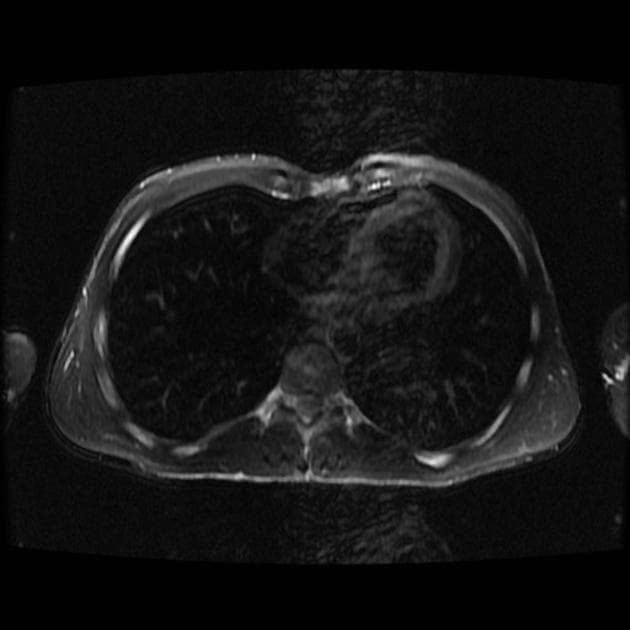

Axial C+ delayed

- Một khối lớn với thành phần dạng đặc và dạng nang, bờ giới hạn rõ dạng thùy xuất hiện tại gan.

- Sau tiêm thuốc cản quang tĩnh mạch, các thành phần dạng đặc của khối cho thấy tăng quang không đồng nhất, không có kiểu ngấm thuốc hướng tâm (centripetal filling).

- "Chẩn đoán hình ảnh thường cho thấy khối lớn, giới hạn rõ, dạng thùy với tăng quang không đồng nhất sau tiêm thuốc cản quang."

Ung thư tuyến nội tiết gan là một khối u thần kinh nội tiết nguyên phát hiếm gặp, hình thành trực tiếp tại gan, khác biệt với các khối u thần kinh nội tiết di căn thường gặp từ đường tiêu hóa. Khối u thường biểu hiện như một khối lớn, giới hạn rõ, dạng thùy với thành phần hỗn hợp đặc và nang. Trên hình ảnh tăng quang, các thành phần đặc cho thấy tăng quang không đồng nhất, không có kiểu ngấm thuốc hướng tâm đặc trưng như ở các tổn thương lành tính (ví dụ: u mạch máu). Do đặc điểm hình ảnh chồng lấn với các khối u gan ác tính khác, chẩn đoán xác định cần dựa vào giải phẫu bệnh và miễn dịch hóa học, với các dấu ấn dương tính như chromogranin A, synaptophysin và CD56. Cắt bỏ khối u hoàn toàn là phương pháp mang lại tiên lượng sống lâu dài tốt nhất.